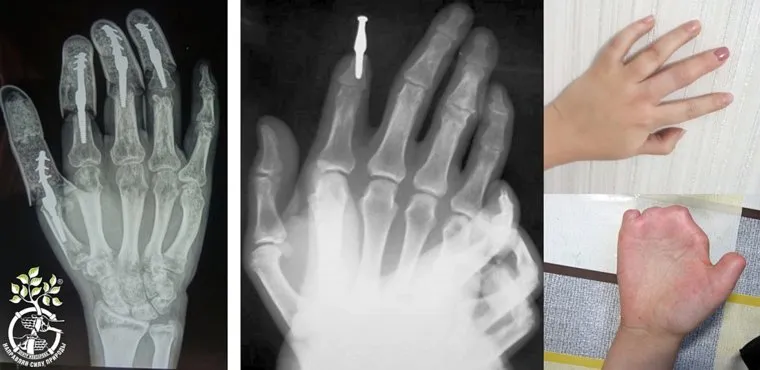

Врачи Центра им. Илизарова совместно с партнерами работают над проектом «Реконструктивная хирургия и экспресс-имплантация» под эгидой Уральского научно-образовательного центра (УМНОЦ). Ученые готовятся к проведению клинических испытаний имплантов и хирургической технологии их установки на месте частично или полностью утраченных пальцев рук, сообщили в пресс-службе Курганского госуниверситета.

«Проект Курганской области „Реконструктивная хирургия и экспресс-имплантация“ из портфеля Уральского научно-образовательного центра приближается к этапу клинических испытаний. Проект направлен на восстановление функций кисти при частичной или полной утрате пальцев за счет оригинальной хирургической технологии и имплантируемых конструкций. За основу взяты возможности персонифицированной медицины. Иными словами, делается то, что нужно конкретному человеку в его конкретной ситуации», — поясняют в КГУ.

В этой работе Центр Илизарова сотрудничает с Уральским федеральным университетом, где изучают возможности применения новых сплавов и новых материалов для имплантов. Например, применение наноструктурированного титана. На предприятии «Сенсор» формируется технология обработки имплантатов, отрабатывается как конструкция изделия, так и сама хирургическая технология — применение метода остеоинтеграции (соединение костных структур периимплантационной зоны с имплантатом).

Заместитель директора по научной работе Центра Илизарова Евгений Овчинников сообщил, что сейчас проводятся доклинические испытания разных модификаций изделия и разных способов имплантации. Врачи участвуют в доработке дизайна изделия и хирургической технологии. Результаты исследований и накопленные знания послужат базисом для создания линейки протезов для восстановления уже не кисти руки, а опорных конечностей, утраченных в ходе боевых действий. Проект «Реконструктивная хирургия и экспресс-имплантация» от Курганской области включен в число прорывных проектов Уральского НОЦ.